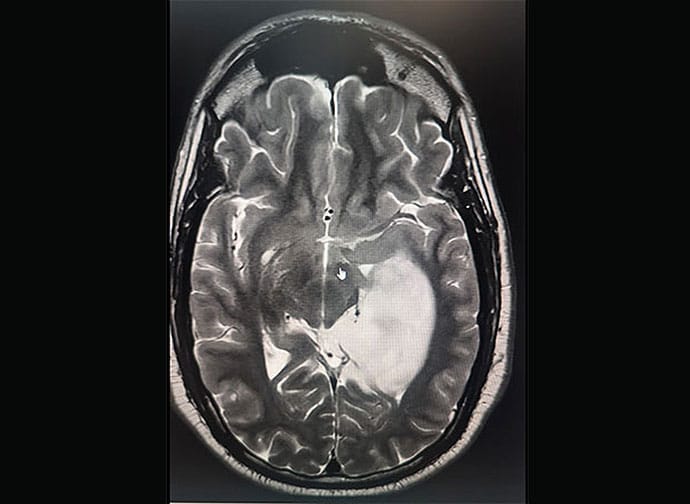

Mukkamala, an otolaryngologist and head and neck surgeon based in Flint, Michigan, was quickly diagnosed with an 8-cm brain tumor in his left temporal lobe, a grade 2 astrocytoma. He’s been on a harrowing journey ever since, maneuvering through both a medical crisis and the troubled American healthcare system.

When I got home [from the meeting in Florida]. A colleague of mine is a neurosurgeon, so at 9 PM I got an MRI. By 9:30 PM, I see that I have a brain tumor — a pretty big one. An 8-cm tumor in the left temporal lobe, the speech center of the brain in most people. Seizure activity within that part of my temporal lobe caused me to speak almost like babbling.